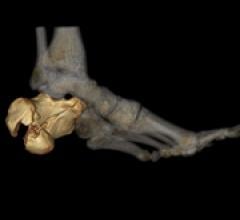

May 10, 2011 – The Methodist Hospital in Houston has taken a significant new step in radiation therapy and surgical planning at the facility’s world renowned Plato’s CAVE (Computerized Augmented Visual Environment). New PhyZiodynamics from Ziosoft, Inc., a pioneer and leader in supercomputing functional analytics, will be used to produce true-fidelity, highly accurate 3-D and 4-D images based on computed tomography (CT), magnetic resonance (MR), and positron emission tomography (PET) scans of the brain, lungs and other organs.

November 10, 2010 – New 4-D functional analytic advanced visualization software will be introduced at the Radiological Society of North America (RSNA) meeting in Chicago. PhyZiodynamic, by Ziosoft, is based upon a supercomputing foundation and provides cutting-edge algorithms for functional imaging analysis across multiple dimensions.